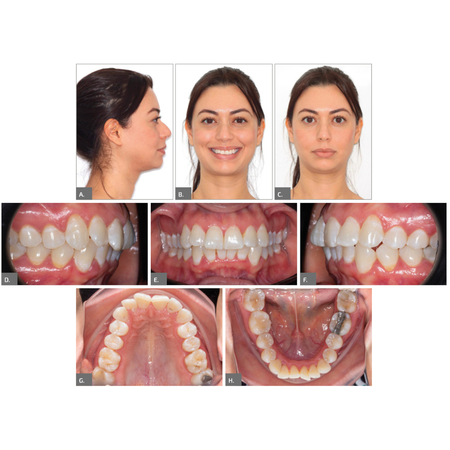

Tratamento ortodôntico-cirúrgico de má oclusão de Classe II esquelética usando alinhadores

OBJETIVO: Relatar o caso clínico de um paciente com má oclusão de Classe II esquelética e dentária, com queixa principal inicial de roncopatia e queixa secundária sobre o perfil e a estética facial (sorriso). RELATO DO CASO: De posse dos elementos diagnósticos, avaliação clínica e facial, optou-se por um tratamento ortodôntico-cirúrgico. Após elaboração do plano digital (ClinCheck®, Align Technology) e recebimento da sequência de 67 alinhadores, seguiu-se com distalização...